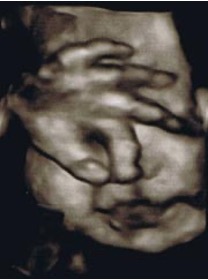

眩しそうに目の前に手をかざす、33週の赤ちゃん。